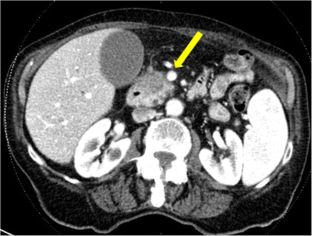

Fig. 1

Fig. 2

Fig. 3

Fig. 4